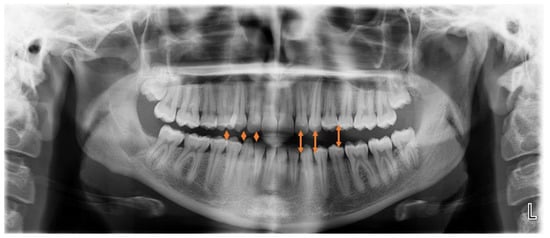

O—open bite at the canine, premolar area (Figure 2)—visible in RTG as the enlarged distance from upper and lower dentition on the HH side;-greatly related to individual factors especially the degree and occurrence time of pathological growth;

Figure 2. Visible open bite and increased vertical distance between upper and lower anterior teeth.